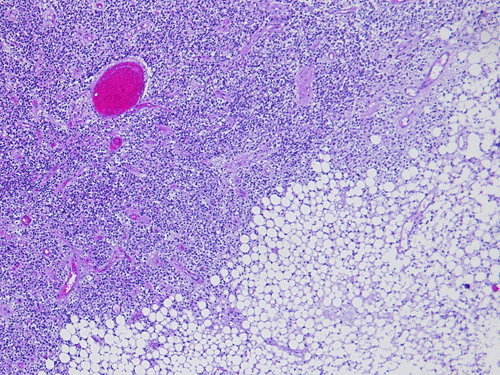

Pathology of the case:  The specimen was fragments of soft tan tissue. The lesion is a cellular neoplasm with solid sheets of cellular component admixed with irregular islands of lipidized cells with morphology of mature adipocytes (Panel A). The two components are well demarcated from each other (Panel B). The cellular component contains predominantly of polygonal cells with round nuclei and minimal nuclear pleomorphism (Panel C and D). Although a perinuclear halo is present in most of the tumor cells, the cytoplasm is not optically clear in some tumor cells and contains a amphophilic, finely granular cytopalsm. Scant amount of neuropils are present. On immunohistochemistry, the cellular component is strongly immunoreactive for syanptophysin ((Panel E).  Immunoreactivity for NeuN is weak and heterogeneous. Some entrapped reactive astrocytes are demonstrated by immunohistochemistry for glial fibrillary acidic protein but both cellular and adipose cell-like components are negative. No immunoreactivity for neurofilament proteins is demonstrated in the tumor cells.

Cerebellar liponeurocytoma have been described in the cerebellar vermis, hemispheres and as tumor that grow into the cerebellar pontine angle. Histologically, the neuronal/neurocytic component is composed of sheets of uniform polygonal cells with round nuclei. Distinct perinuclear halo similar to those being seen in oligodendroglioma and central neurocytomas are present in the neuronal/neurocytic component. This would lead to a honey comb pattern under low- or medium-magnification.  Some of these cells may also have amphophilic granular cytoplasm. Neuropil formation can be focally seen. The lipidized component is morphologically indistinguishable from mature, adult type of adipose tissue  in other part of the body. Histologic variation between different tumors do not appear to be substantial.